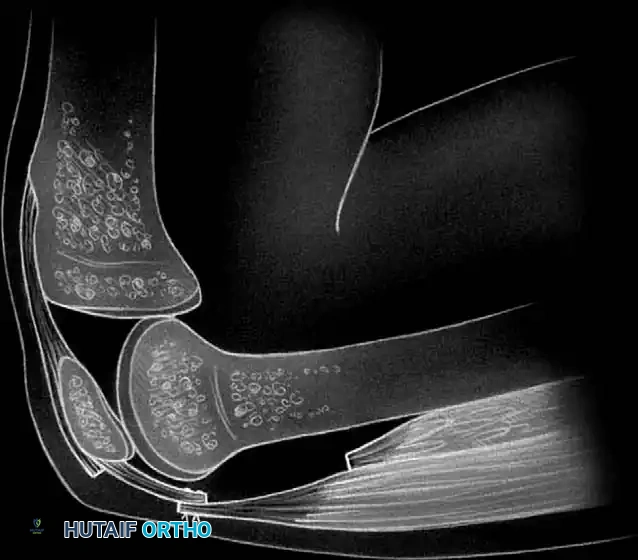

STAGE 5: Quadriceps Tendon Lengthening

* The fifth and final stage consists of a formal lengthening of the quadriceps tendon.

* Transect the rectus femoris at a more distal level than the vastus intermedius, adjacent to its patellar insertion.

* Deliver the free tendinous ends of the vastus intermedius and rectus femoris through the percutaneous wound.

- Gently manipulate the knee in flexion repeatedly until maximal flexion is achieved. The proximal portion of the vastus intermedius tendon and the distal portion of the rectus femoris tendon are then sutured together with the knee held in 90 degrees of flexion to set the new resting length of the extensor mechanism.